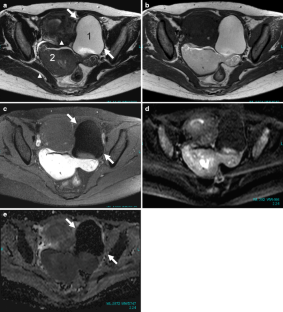

Fig. 8a–e